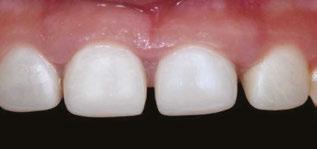

Several clinical solutions exist for primary anterior teeth with multisurface decay. Full coronal restoration of carious primary incisors may be indicated when caries is present on multiple surfaces, pulpal therapy is indicated, caries may be minor, but oral hygiene is very poor, or in a child with severe early childhood caries or a high caries risk diagnosis.1 Depending on the clinical scenario, a minimally invasive approach with the utilization of a high viscosity glass ionomer cement (HVGIC), with or without the combination of silver diamine fluoride (SDF) in a strip crown form, may pause the caries progression and provide an adequate clinical solution. Resin composite strip crowns have shown 80% retention rates and adequate parental satisfaction,1-4 although composite resin strip crowns have shown lower retention rates in teeth with decay involving three or more surfaces and particularly in children with a high caries risk4-6 (Figure 1). This could be from the continued high caries risk behaviors of the patient, as composite resin strip crowns in this population have shown to have increased inflamed marginal gingiva and gingival bleeding, increased plaque retention along the restoration, and loss of some restorative material.5,6

Alternatively, a resin-faced stainless steel crown provides a full coverage restoration with excellent retention.7 These crowns can serve as a full-coverage restoration with or without the resin facing, but the loss of resin facing can be a major esthetic concern for parents.7 Preformed pediatric zirconia crowns address many of the undesirable clinical outcomes of other restorative materials. Their biocompatibility, demonstration of excellent marginal gingival health, low plaque retention, high parental esthetic acceptance, and high survival probabilities make them an excellent clinical choice in the patient with severe early childhood caries.1,4,5,8-13

With parental interest increasing in esthetic treatment options for complex anterior caries, preformed pediatric zirconia crowns are becoming the treatment of choice for patients with a high caries risk or a severe early childhood caries diagnosis.14

This review discusses three clinical cases in which NuSmile® ZR (NuSmile, Houston, Texas) anterior pediatric zirconia crowns were the correct clinical decision in varying clinical scenarios.

around these clinical sites. His anterior zirconia crowns showed healthy gingival margins with little-to-no plaque accumulations. This positive clinical finding is from the highly polished nature and biocompatibility of pediatric zirconia crowns. These restoration features limit plaque accumulations on the restoration and along the marginal gingiva, providing a localized positive aspect directly related to the choice of restorative material (Figure 2).

Case 2

A 3-year-old female presented with pulpal necrosis and abscess on #E and pulpal necrosis on #F. Extraction therapy or pulpectomy was offered. The family was highly motivated to retain #E and #F. The pulpectomy was performed with 0.02 K-Flex hand files, 3% NaOCl with a lateral vented needle, obturated with Vitapex (Neo Dental International Inc., Federal Way, Washington), a premixed paste of calcium hydroxide and iodoform. The access was filled with a HVGIC sealing the pulp therapy and increasing the clinical success by minimizing the potential for bacterial contamination. NuSmile ZR anterior crowns were selected as offering a full-coverage, esthetic, cemented restoration with no polymerization shrinkage when compared to a composite restoration. Crowns were cemented with NuSmile® BioCem (NuSmile, Houston, Texas). This is clinically beneficial as the provider would want to cement a restoration that provides limited microleakage minimizing the potential for bacterial contamination.15-17 At 6-month follow up, lesion healing had occurred with healthy gingival margins and no plaque accumulations (Figure 3).

Figure 3: NuSmile® ZR Crowns were selected as a cementable full coverage restoration. At 6-month recall, apical tissues were healed with excellent gingival health Figure 4: SMART style restorations that were definitively restored with NuSmile® ZR Crowns as an esthetic option to cover SDF staining